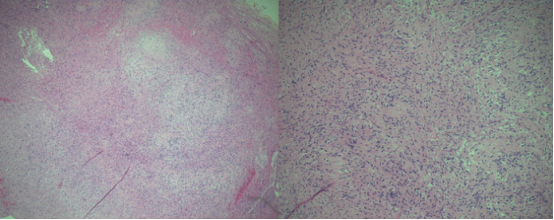

蘇木精- 伊紅染色的組織學(xué)標(biāo)本顯示細(xì)胞區(qū)域含柵欄狀排列的細(xì)胞核(安托尼 A 型),交替出現(xiàn)少細(xì)胞區(qū)域由疏松水腫間質(zhì)中不規(guī)則排列的細(xì)胞構(gòu)成(安托尼 B 型)。